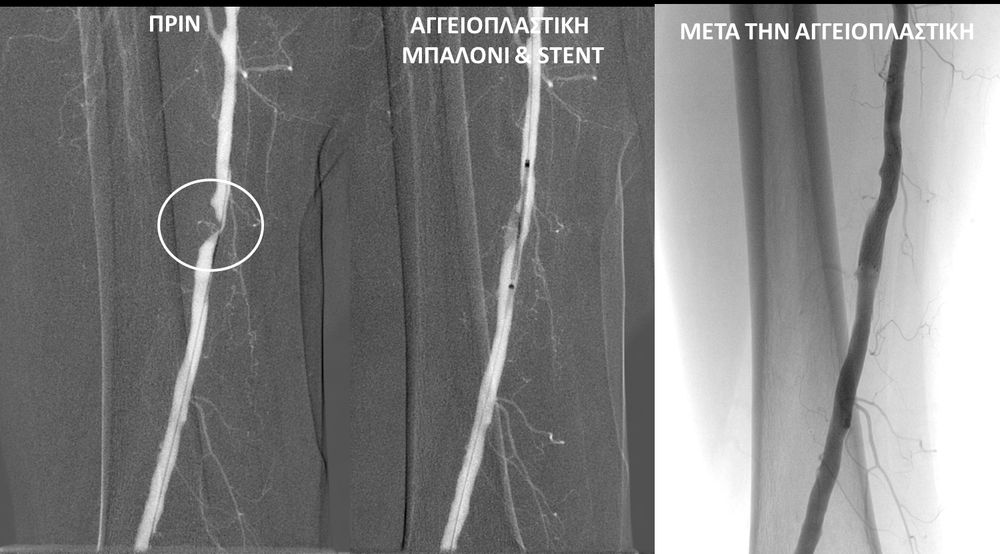

• Η αγγειοπλαστική των αρτηριών είναι μία μη χειρουργική επέμβαση που αποσκοπεί στη διάνοιξη των στενωμένων ή αποφραγμένων αρτηριών. Γίνεται με την ίδια τεχνική όπως και αγγειογραφία. Η αγγειοπλαστική των αρτηριών μπορεί να γίνει είτε με απλή διάνοιξη της αρτηρίας που εμφανίζει στένωση με μπαλόνι ή και να συνοδευθεί από τοποθέτηση ενδαγγειακής πρόθεσης (stent).